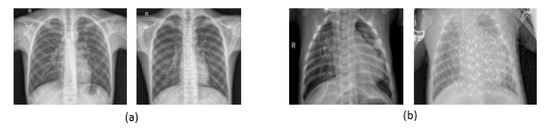

6.1. Dataset